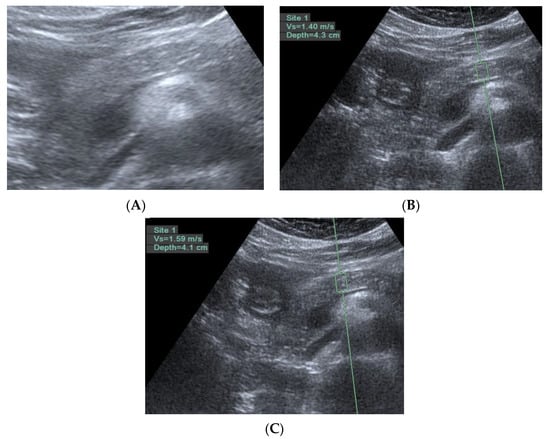

Figure 5.

Three trans-abdomen sonographic images of the pancreas in the same patient. (A) Some hyperechoic foci in the pancreas; (B) if there are no hyperechoic foci in the region of interest, the pancreatic ARFI is 1.4 m/s; and (C) if there are hyperechoic foci in the region of interest, the pancreatic ARFI is higher (1.59 > 1.4 m/s).